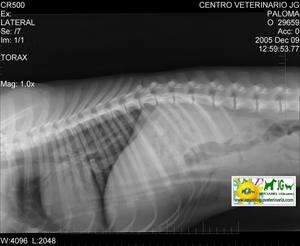

Radiografía con contrastes: mielografía por saco dural | |||||||||

![]() por Juan M. Griñán. Veterinario ![]() comparativa entre una mielografía (mostrando la aguja) y una resonancia magnética, secuencia SE T1w (mostrando donde está el saco dural, sitio para la inyección del contraste). Nótese la extravasación del contraste yodado en la mielografía. | |||||||||